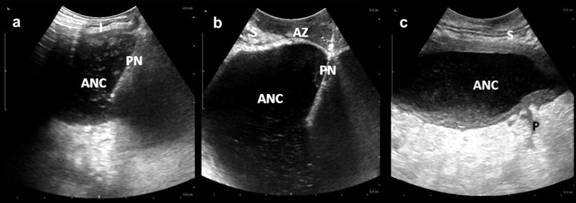

The main disadvantage for all types of MIT approaches is the necessity to repeat the MIT procedures and a relatively high complication rate. The current study demonstrates surgical intervention based on a wider use of ultrasonography as a navigation tool in ultrasound-assisted surgery. The unique aspect of this strategy is the application of the ultrasonography method used by the surgeon who specializes in the field of ultrasonography and may use the full potential of this method by starting from a percutaneous ANC drainage, control of the complete drainage and intraoperative ultrasound navigation through small 4-6 cm incisions in the abdominal wall to find the right anatomical plane and localize the fluid collections or necrosis, and following with necrosectomy and drainage. Our strategy allows the use of the sinus tract created during the first intervention for repeated debridement in the ICU, similarly to what has been recently reported [45]. The important experience is the combination of the step-up approach and ultrasound-assisted surgery to provide open necrosectomy but with minimal access elements or FON. This strategy gives the opportunity to provide surgical treatment to patients with wide peripancreatic and bilateral retroperitoneal involvement as well [10]. Simple criteria give the possibility to select the patient for FON. These include: previous PD of ANC, localized process confirmed by CECT and transabdominal ultrasound before intervention in patients with evidence of the progression of sepsis and organ dysfunction, despite conservative treatment. The use of these criteria is supported by a number of other studies [4, 19, 28, 46]. We did not use fine needle aspiration for bacterial culture assessment, which has been recently recognized as an inapplicable diagnostic tool [4, 28, 41]. Finally, the main outcomes of our study comply with the study results reported by different authors. The postoperative complication rate [24, 47-49] and mortality is similar to other reports concerning the MIT approaches [19, 24, 25, 50] and the conventional approach [15, 36, 48]. The rate of preoperative infection which is the main determinant of the late mortality is in the same range as reported by a number of other studies. Nevertheless, a higher prevalence of bacteraemia was observed in patients who underwent conventional surgery, probably indicating poorly localized infected necrosis (Figure 3).

Figure 3. Intraoperative ultrasonoscopy assisted drainage of acute necrotic collection (ANC). a. I: intestine; PN: puncture needle). b. S: Stomach; PN: puncture needle; AZ: avascular zone. c. S: stomach; P: pancreas. |